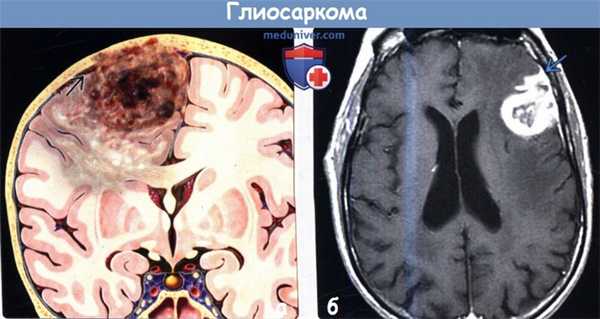

(а) На рисунке коронального среза показано периферически локализованное объемное образование с инвазией в твердую мозговую оболочку и прилегающие кости черепа.

Образование имеет гетерогенную структуру за счет некротического компонента. Указанные признаки характерны для глиосаркомы. За счет инфильтративного характера роста опухоли также наблюдается вовлечение мозолистого тела.

Инвазия в твердую мозговую оболочку с возможным вовлечением костей черепа помогает отличить этот вариант глиобластомы (МГБ) от типичной МГБ.

(б) МРТ, постконтрастное Т1-ВИ, аксиальный срез: в лобной доле определяется толстое периферийное контрастирование гетерогенного объемного образования с его инвазией в твердую мозговую оболочку, что характерно для глиосаркомы. (а) МРТ, Т2-ВИ, аксиальный срез: у мужчины 57 лет в правой лобной доле определяется гетерогенное объемное образование.